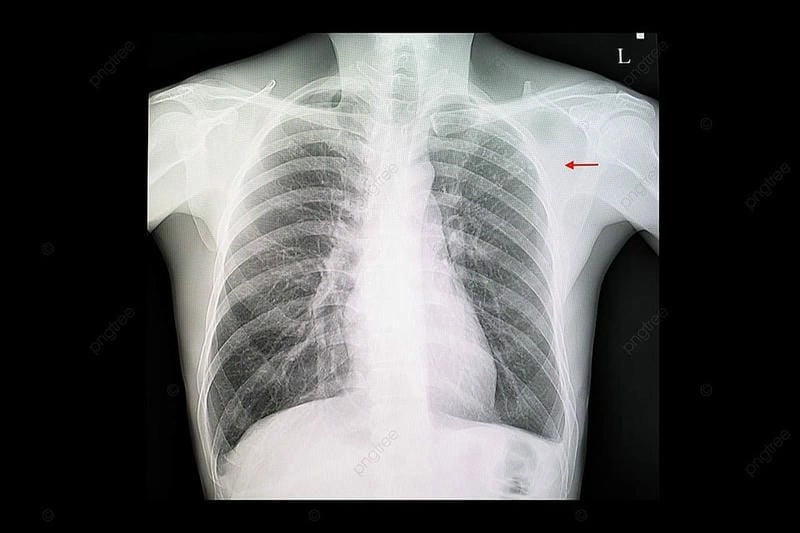

Bạn sẽ phải rùng mình khi chiêm ngưỡng hình ảnh bệnh lao phổi là như thế nào dưới ống kính y học thực tế. Những bức ảnh chụp X-quang cho thấy phổi bị tổn thương nặng, xuất hiện những đốm trắng mờ như bóng ma ám ảnh. Không chỉ là các tổn thương vật lý, đây còn là những “chứng tích sống” của căn bệnh âm thầm hủy hoại cơ thể qua từng hơi thở. Từ viêm nhẹ đến tổn thương lan rộng, hình ảnh bệnh lao phổi khiến người xem không thể rời mắt vì mức độ nghiêm trọng mà nó thể hiện rõ ràng qua từng chi tiết.

Cảnh báo: tổng hợp ảnh bệnh lao phổi chân thực này không dành cho người yếu tim. Đây là loạt hình ảnh y khoa được các chuyên gia sưu tầm và xác thực, ghi lại quá trình tiến triển của bệnh từ giai đoạn đầu đến giai đoạn nguy kịch. Từng mảng mô phổi bị ăn mòn, xơ hóa, hoại tử được phơi bày rõ nét dưới ánh sáng X-quang lạnh lùng. Những hình ảnh này không chỉ mang tính chất minh họa y học, mà còn là hồi chuông cảnh tỉnh cho bất kỳ ai còn lơ là với căn bệnh nguy hiểm này.